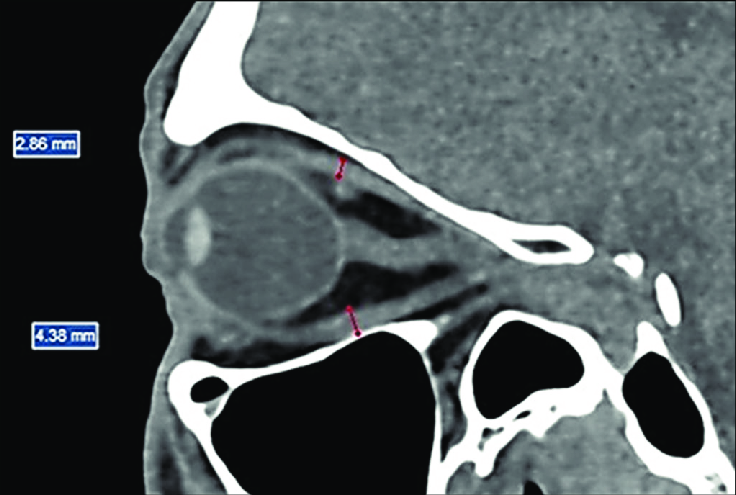

A órbita é uma estrutura complexa formada por múltiplos ossos e contendo estruturas nobres como o globo ocular, músculos extraoculares e nervo óptico. A TC é o método de escolha para avaliação de trauma e patologias orbitárias.

Figura 2: Corte sagital de TC de órbitas mostrando estruturas anatômicas

Conteúdo Orbitário

- Globo ocular

- Músculos extraoculares

- Nervo óptico

- Gordura orbitária